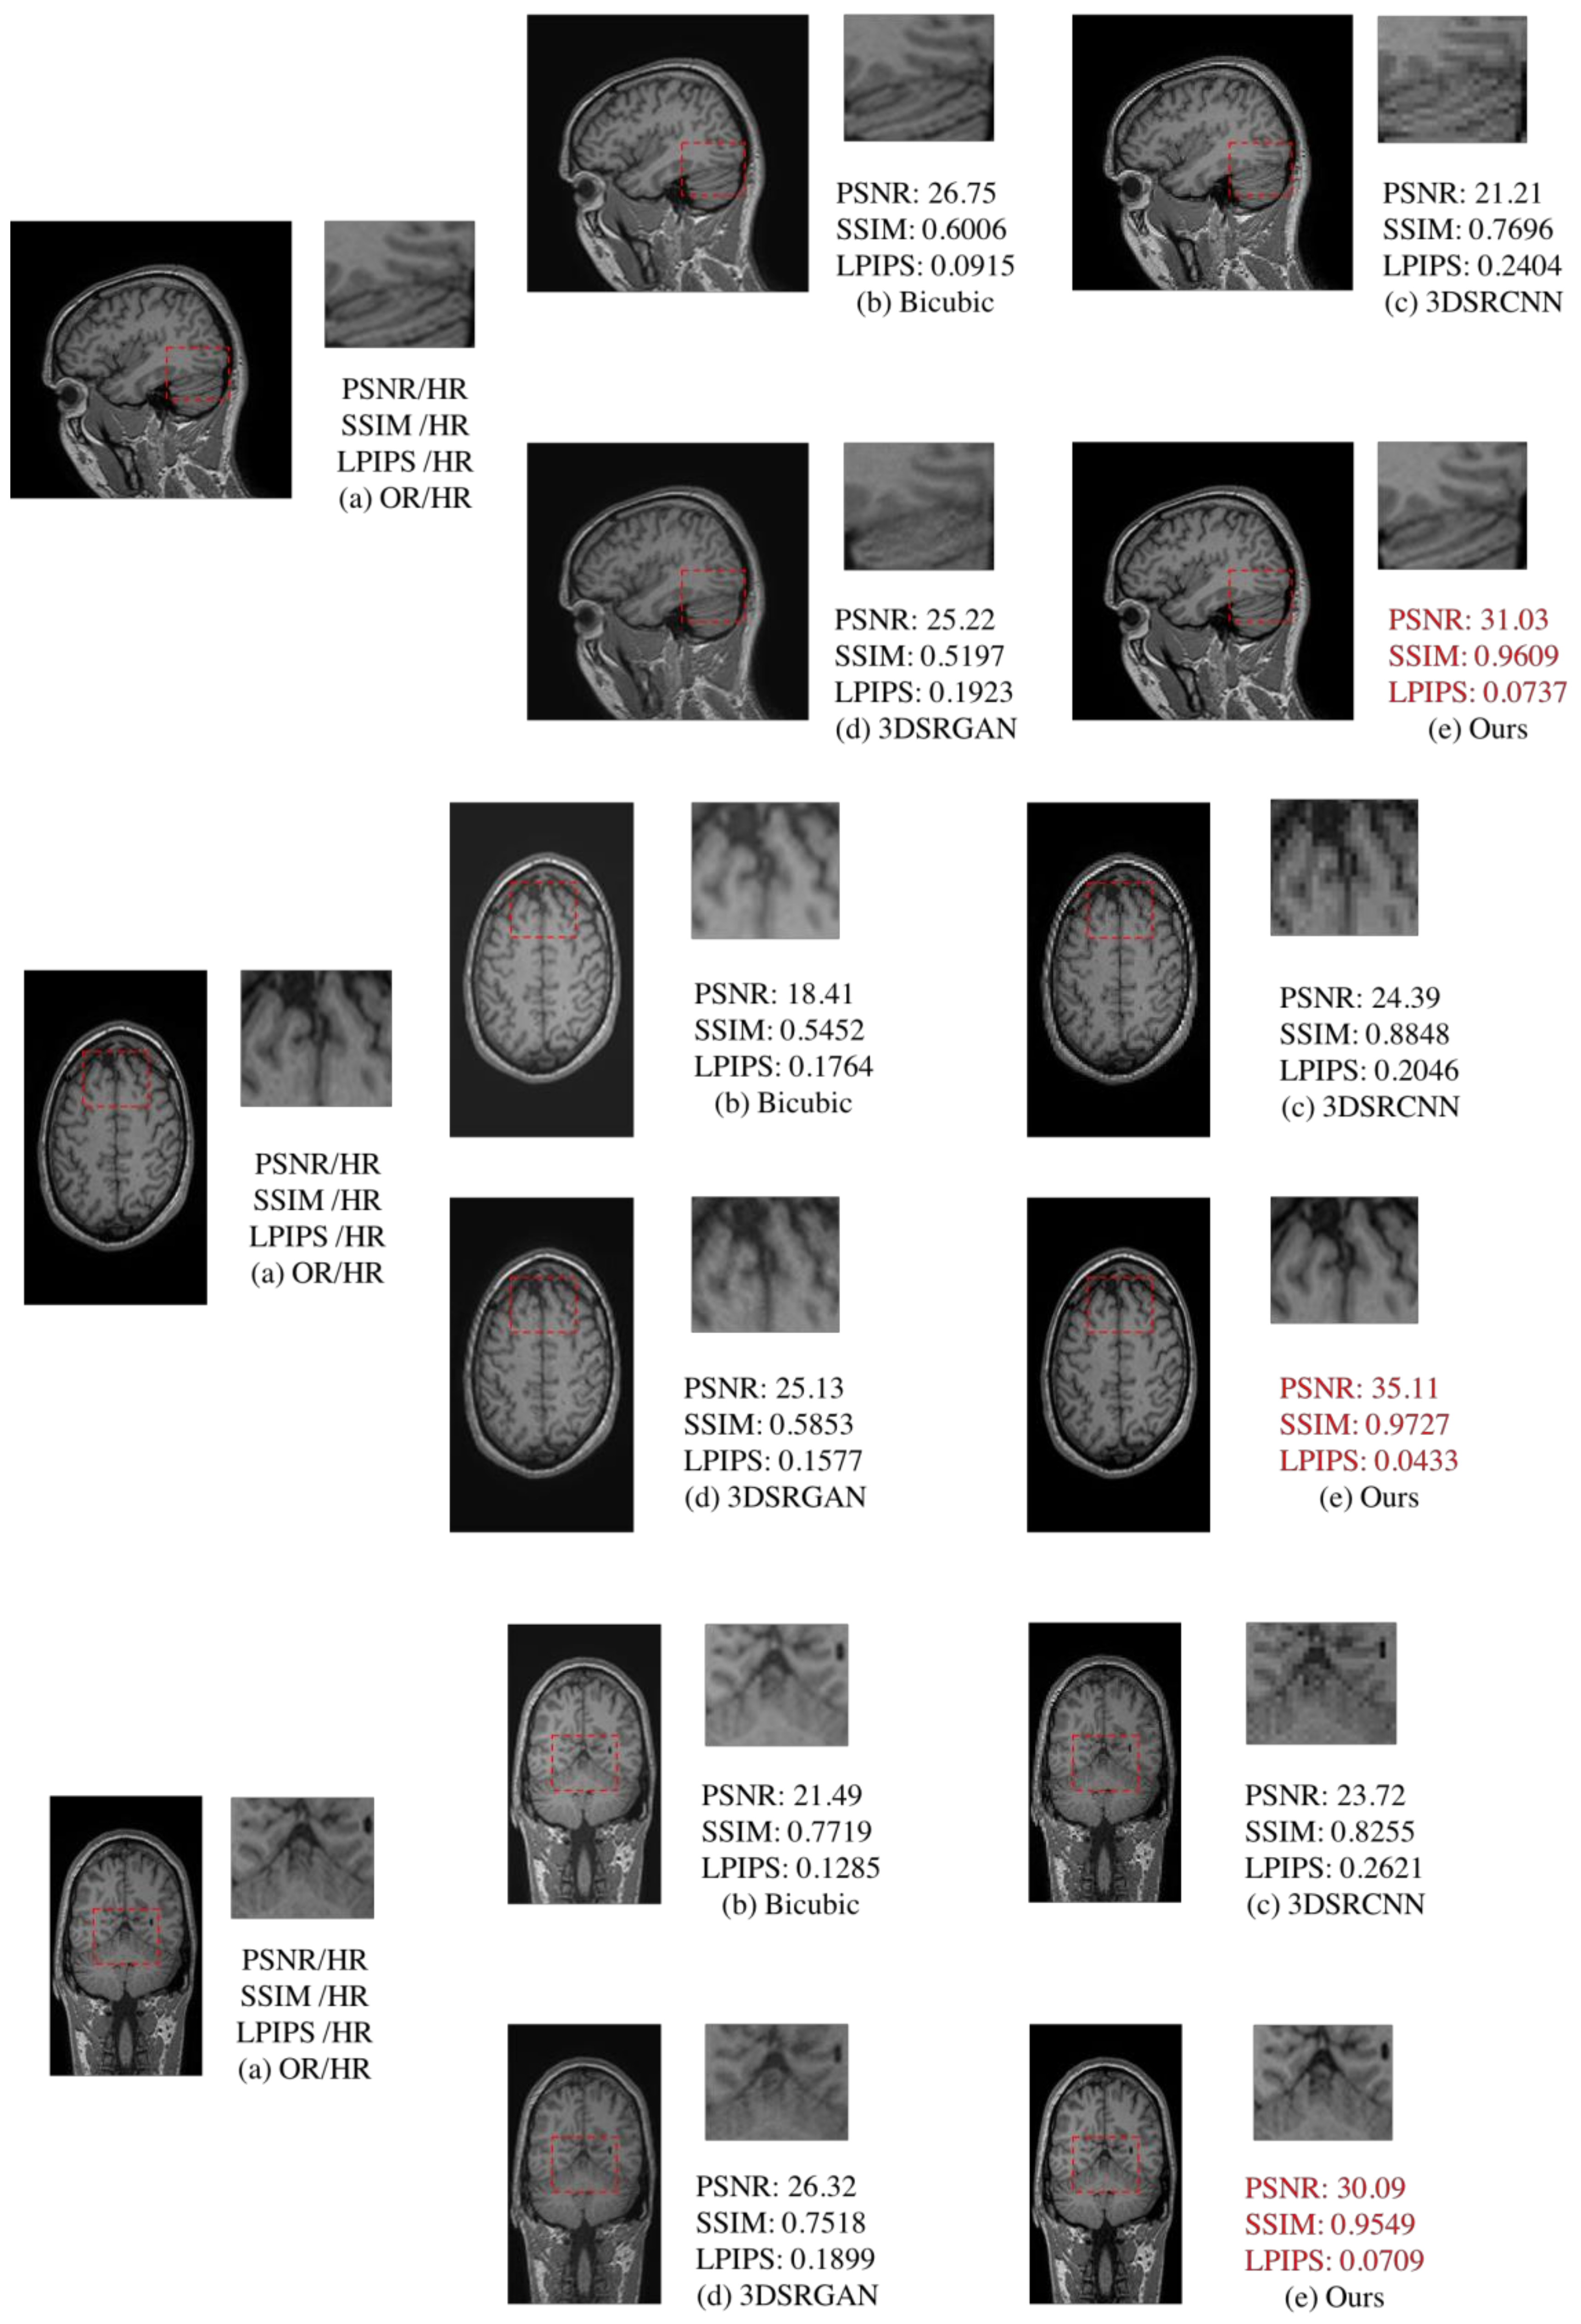

4.3. Comparison of 2D and 3D

| Plane/Network | Evaluation | Bicubic | 3DSRCNN | 3DSRGAN | Ours |

|---|---|---|---|---|---|

| Sagittal | PSNR ↑ | 25.77 ± 1.32 | 19.93 ± 0.9728 | 23.74 ± 1.13 | 30.28 ± 0.59 |

| SSIM ↑ | 0.8170 ± 0.0191 | 0.7240 ± 0.0346 | 0.7288 ± 0.0145 | 0.9497 ± 0.0020 | |

| LPIPS ↓ | 0.1321 ± 0.0103 | 0.3288 ± 0.0150 | 0.2236 ± 0.0102 | 0.0806 ± 0.0039 | |

| Coronal | PSNR ↑ | 19.44 ± 2.12 | 24.02 ± 0.72 | 24.74 ± 1.34 | 34.25 ± 1.34 |

| SSIM ↑ | 0.6318 ± 0.0315 | 0.8838 ± 0.0183 | 0.6422 ± 0.0287 | 0.9710 ± 0.0022 | |

| LPIPS ↓ | 0.1550 ± 0.0265 | 0.2300 ± 0.0127 | 0.1723 ± 0.0149 | 0.0498 ± 0.0059 | |

| Axial | PSNR ↑ | 23.71 ± 1.69 | 25.08 ± 1.73 | 27.43 ± 1.84 | 30.93 ± 0.90 |

| SSIM ↑ | 0.6901 ± 0.0299 | 0.8634 ± 0.0642 | 0.7065 ± 0.0549 | 0.9596 ± 0.0053 | |

| LPIPS ↓ | 0.1236 ± 0.0233 | 0.2471 ± 0.0234 | 0.1486 ± 0.0272 | 0.0731 ± 0.0121 |